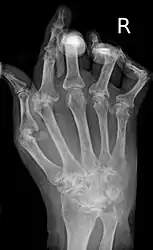

| A hand severely affected by rheumatoid arthritis. This degree of swelling and deformation does not typically occur with current treatment. | |

X-ray of the hand in rheumatoid arthritis.